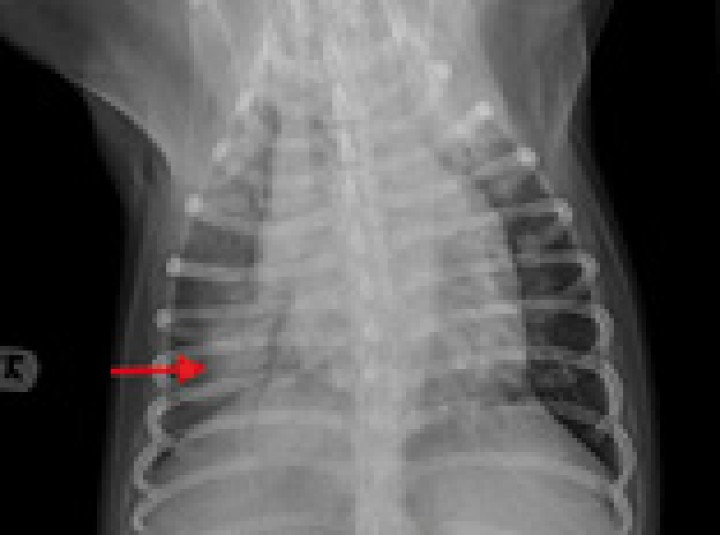

Figura 7

Radiografía dorsoventral de tórax de un perro con fallo cardiaco congestivo secundario a una cardiomiopatía dilatada. Se observa cardiomegalia y patrón alveolar en el lóbulo caudal derecho compatible con edema pulmonar de origen cardiogénico (flecha roja).